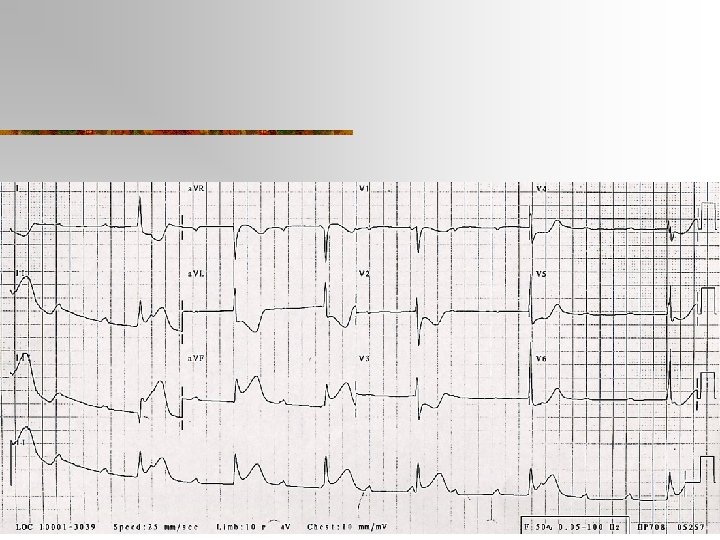

Causes of Cardiogenic APO (acute decompensated heart failure) n n n Myocardial ischaemia/infarction Acute valvular dysfunction Anaemia Arrhythmias Medication non-compliance Dietary, physical or emotional excess Fluid overload- may be iatrogenic Medication adverse effect (neg inotropy of CCB, BB) Myocarditis Pulmonary embolus Progression congestive cardiac failure

Evaluation n ABC n History n Examination n Investigations